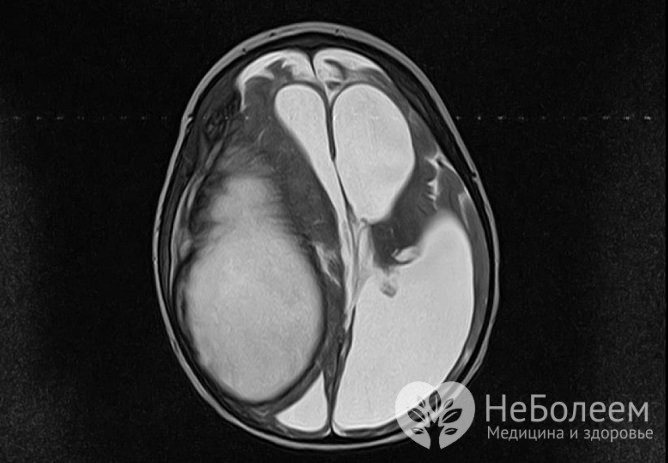

- По снимкам КТ/МРТ зачастую сложно отличить гнойную полость от доброкачественных и злокачественных новообразований, поэтому ее относят к категории потенциально угрожающих жизни состояний.

Заболевание сложно диагностировать, так как симптоматика похожа на проявления других недугов. Лабораторные исследования малоэффективны для диагностики абсцесса мозга. Повышенные показатели СОЭ, белка характерны для многих воспалительных процессов. Бакпосевы при наличии гнойного очага в тканях мозга стерильны. Установить очаг поражения можно с помощью КТ и МРТ.

Компьютерная томография (КТ) эффективна после 3 суток начала болезни. На более ранних сроках выявить очаг гнойного поражения сложно. Это объясняется тем, что введенное контрастное вещество неравномерно распределяется и большая часть его накапливается на периферических участках. Центр заполняется по остаточному принципу.

С развитием энцефалита очаг становится более четко выраженным, его контуры принимают ровные и округлые очертания. Контрастное вещество равномерно заполняет полость, и картина поражения выявляется четко. Абсцесс мозга виден как очерченное образование с высокой плотностью (капсула).

В центре образования находится гной и плотность в этом месте меньше. Хорошо просматривается зона отека, находящаяся на периферии. Контрастное вещество находится по периметру фиброзной капсулы.

МРТ

Наиболее точную картину состояния тканей мозга дает магнитно-резонансная томография. Результат обследования не зависит от стадии развития болезни. Ткани мозга хорошо просматриваются с симптомами, присущими каждому этапу развития патологии.

Так как симптомы, которыми характеризуется абсцесс, не имеют определенной специфики и схожи с таковыми при других мозговых поражениях, важна дифференциальная диагностика. Обычно она заключается в проведении томографии с контрастом – МРТ или КТ.

На ранних стадиях оптимальной является МРТ, так как КТ может «не заметить» воспаление ткани. На этапе инкапсуляции компьютерная томография становится информативной. Как правило, периферия очага на снимке принимает круглые очертания, так как контрастное вещество накапливается по контуру капсулы. На ранних этапах на МРТ-изображениях оценивается интенсивность сигнала энцефалитического очага.